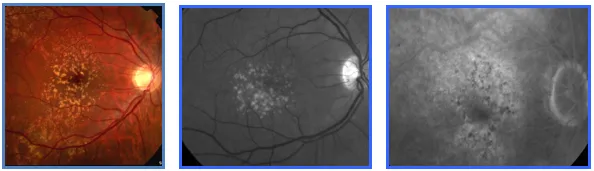

• C'est le stade précurseur de la DMLA qui se caractérise par l'apparition de fins dépôts amorphes dans la rétine aux deux yeux, appelés "Drusen", pouvant s'associer à quelques anomalies de la pigmentation rétinienne.

2.DMLA:Drusen Séreux

• Les dépots dans la rétine sont plus nombreux et de plus grandes tailles(Drusen séreux)

• Ces dépôt peuvent être confluents , coalescents et s'associer à des anomalies de la pigmentation rétinienne

• A ce stade , des légères déformations des lignes droites peuvent être perçues associées à des variations de la vision en fonction de la luminosité .

3.DMLA: Coalescence des Drusen et DEP Drusénoïde